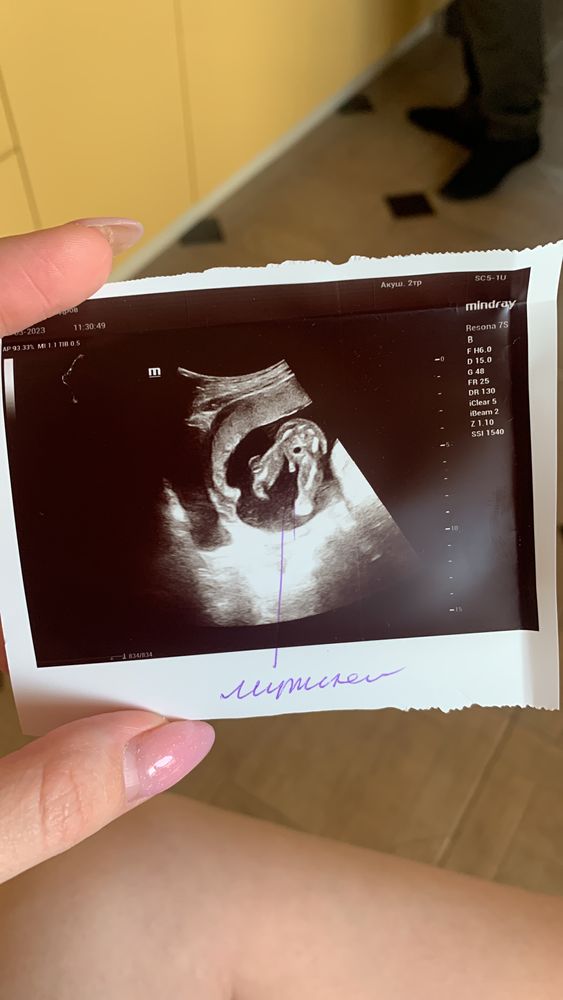

Девочка конечно)) ну где тут мальчик то. Вот мое УЗИ с мальчиком )))

Ну тут прям четко пирожок видно же😁 девочка 100%. У мальчиков уже пипка торчит на таких сроках, не спутаешь точно)

100% девочка. У моей на узи в 21 неделю точно такая же складочка между ножками😀 Но у меня еще нипт на 11 неделе указал, что девочку ждем. Так что , сомнений нет.